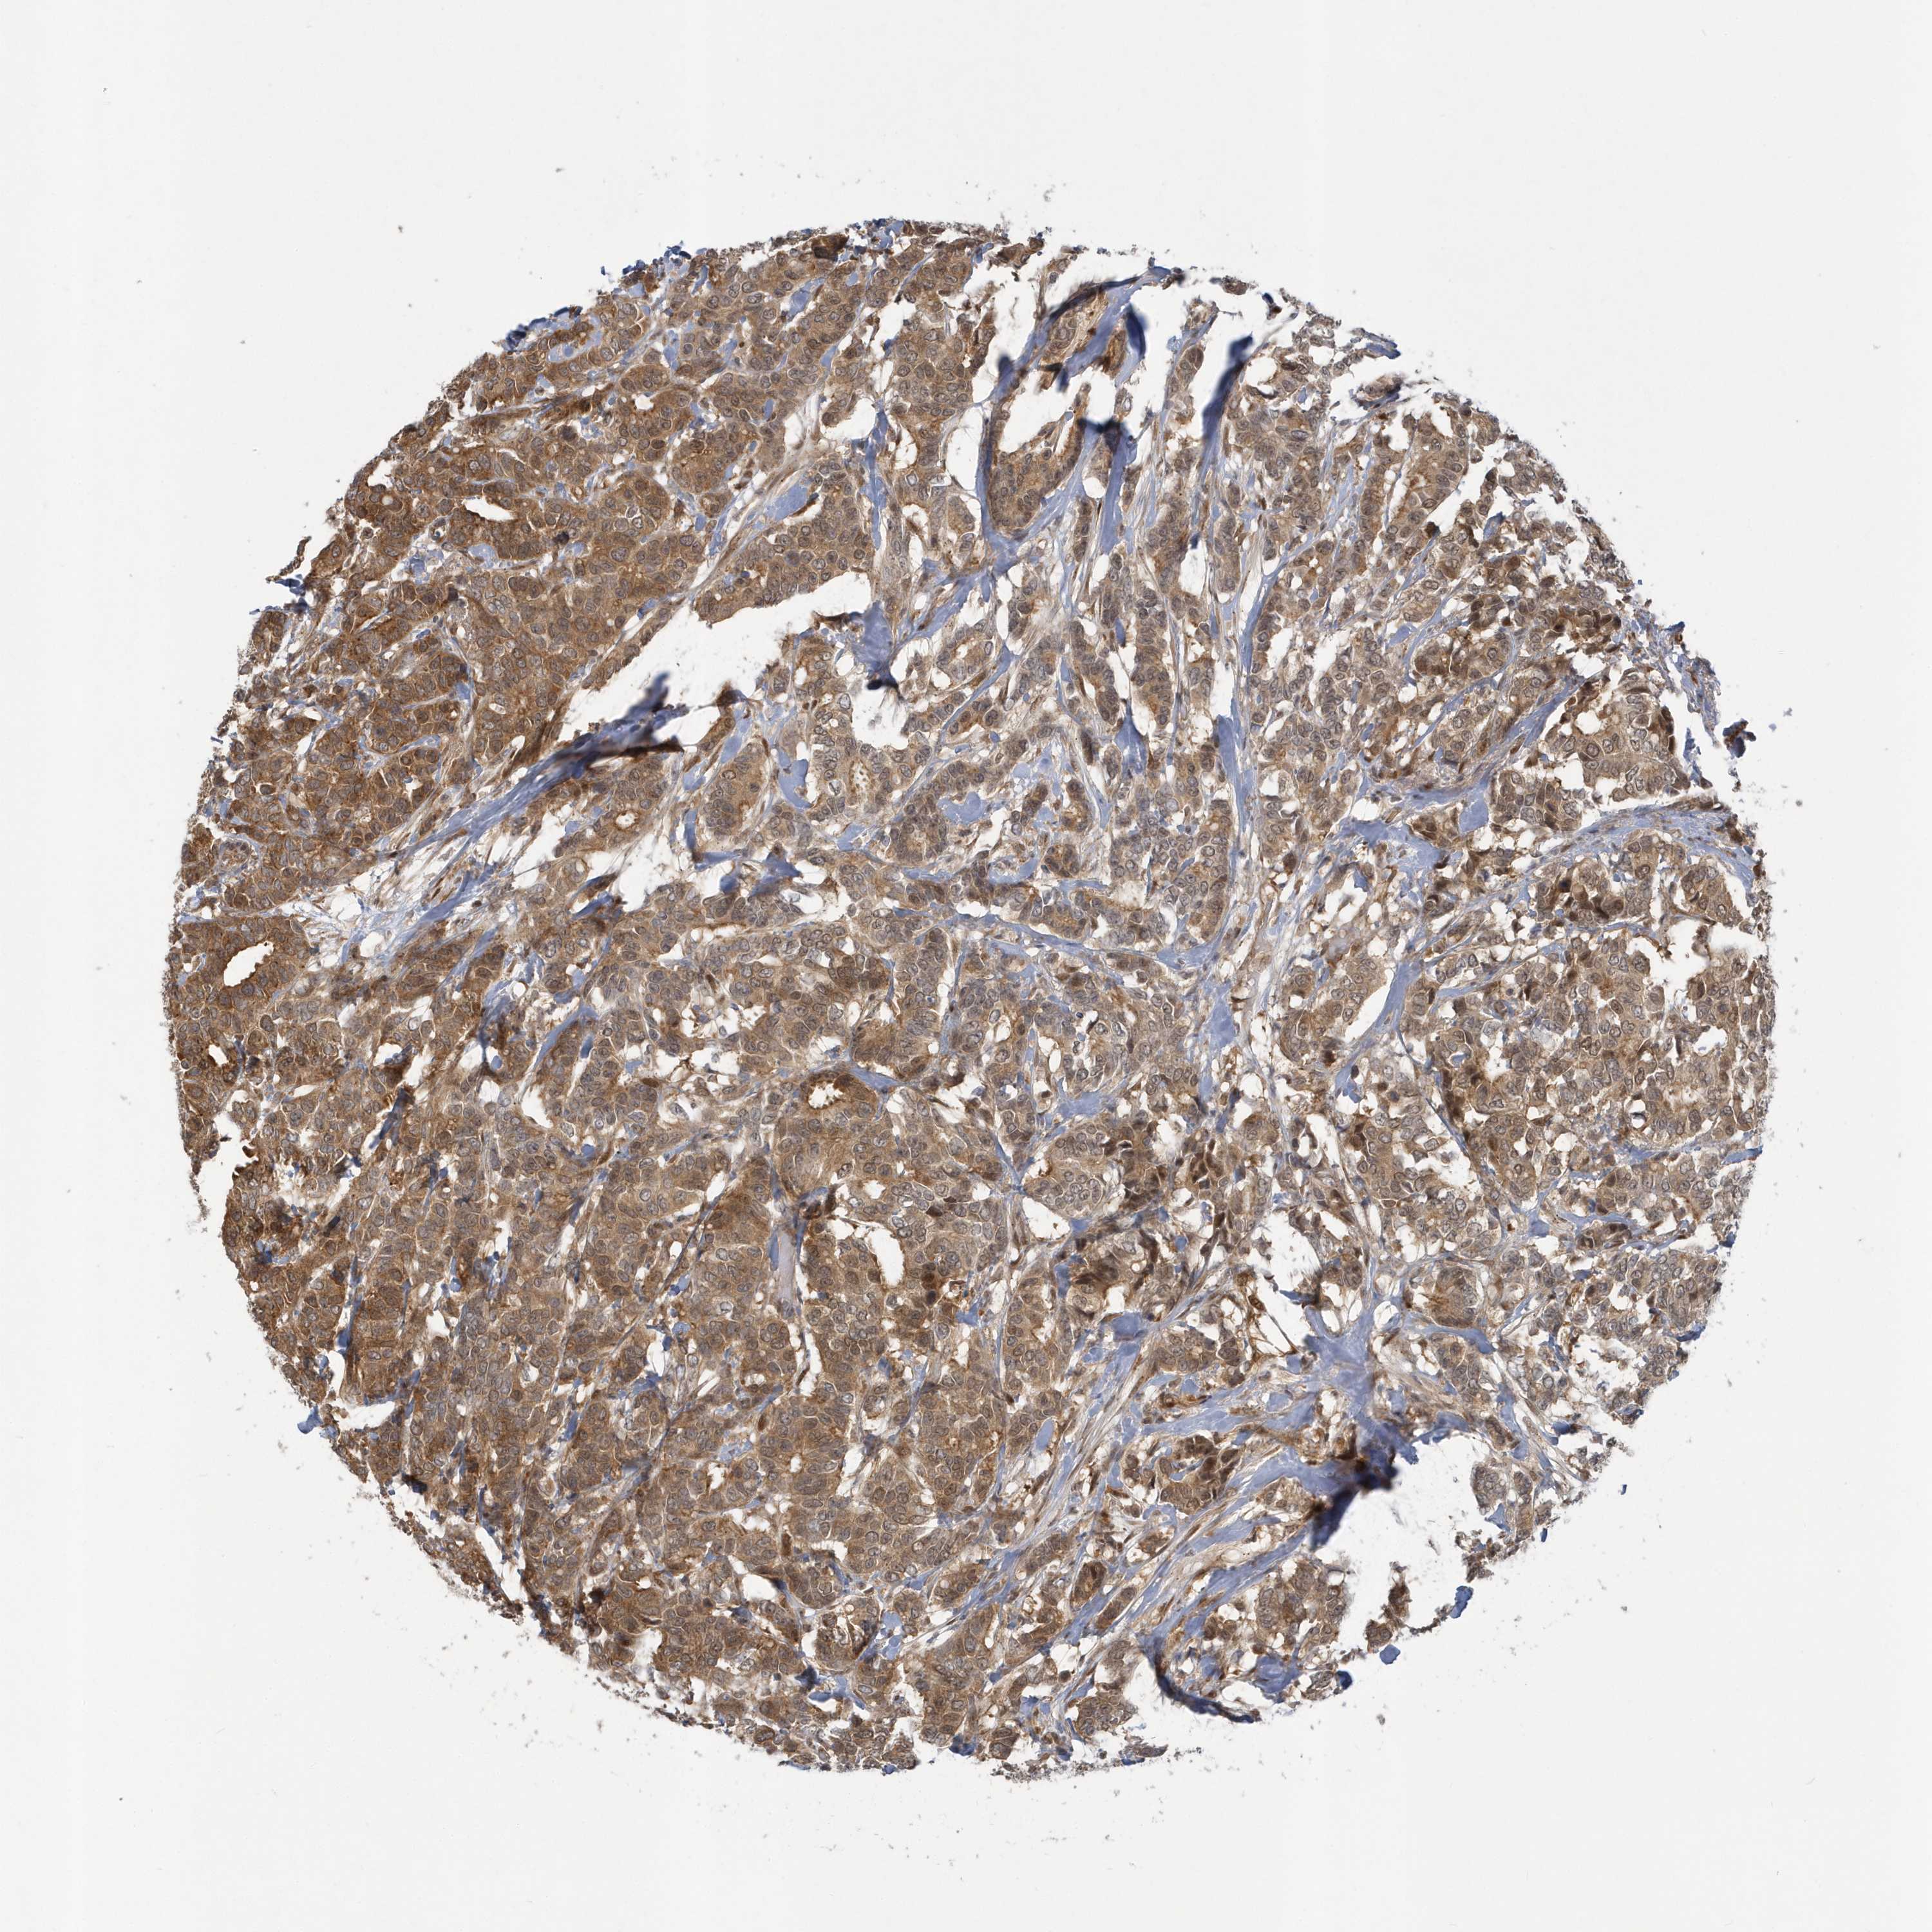

CANCER BREAST CANCER Show tissue menu

BRCA TCGA BRCA VALIDATION PROTEIN EXPRESSION